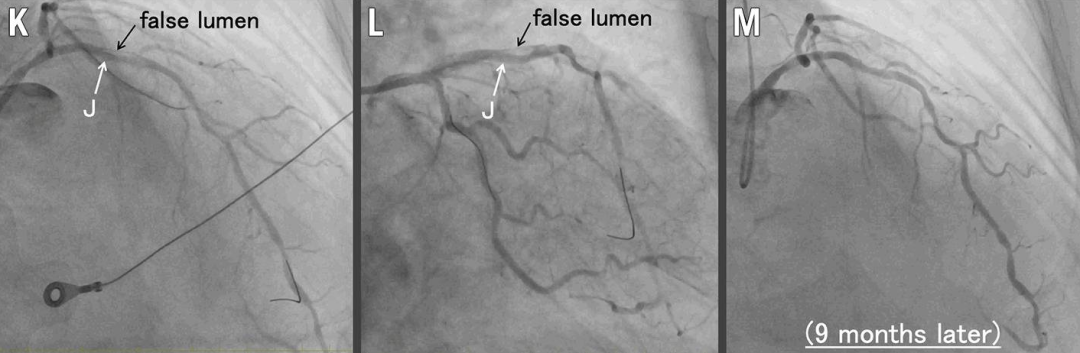

J. IVUS:真腔扩大,多通道形成

K-L. 灌注球囊术后:最终冠状动脉造影,残余假腔存在

M. 9个月随访冠脉造影:夹层愈合

在疑似夹层远端处,也以额定压力扩张灌注球囊以建立真-假腔交通,实现开窗(图 1I)。IVUS显示真腔扩大,真腔与假腔之间有多个连通,随后胸痛和 ST 段抬高缓解(图 1J、视频4)。冠状动脉造影显示LAD血管腔扩大,血流恢复至 TIMI 3 级。

左主干-LAD及LCX行药物球囊扩张后,冠状动脉造影显示结果良好,但残余假腔存在(图 1K、图 1L)

2个月复查冠脉造影:仍有残余假腔

9个月复查冠脉造影(图1M):管腔通畅,夹层完全愈合